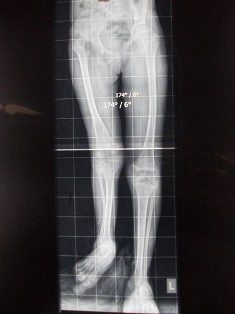

Lengthening of Bone